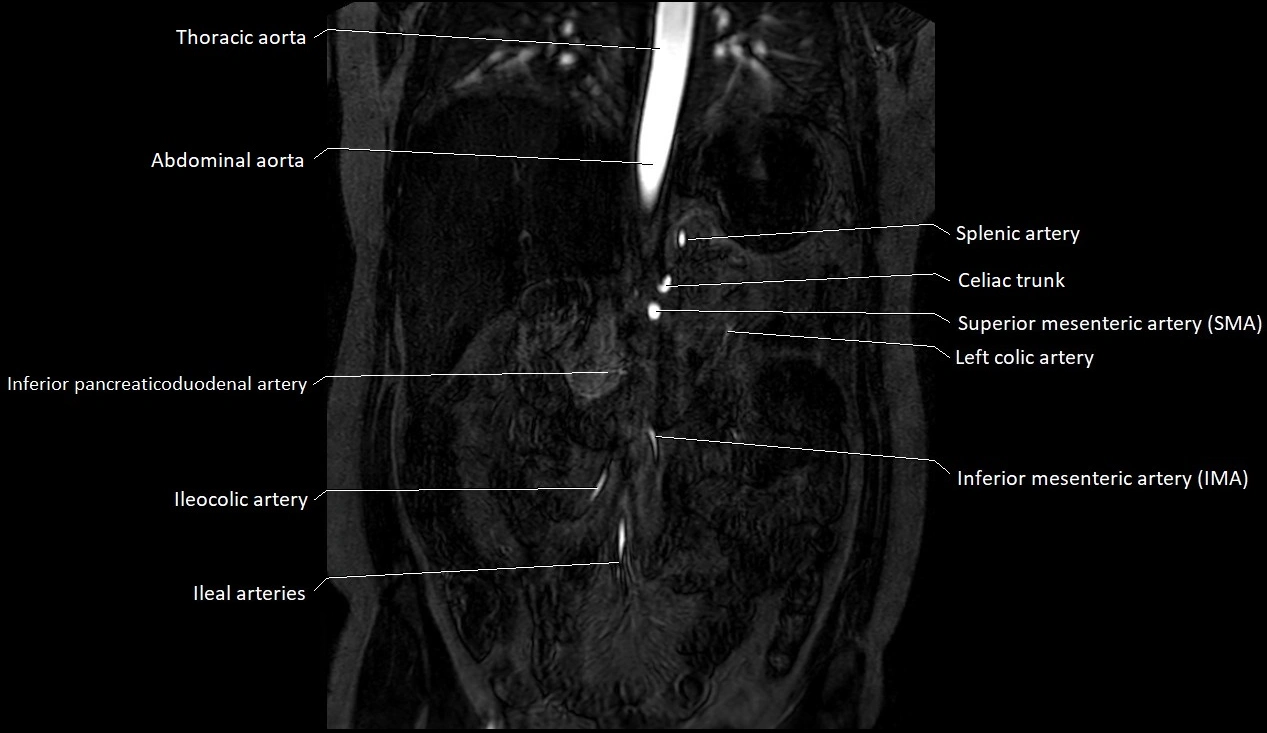

CT images

image